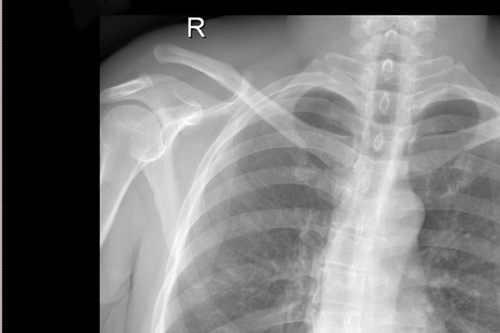

术后DR

一名50岁的男性患者,因不慎摔伤致右肩关节肿痛,并伴活动受限4天后来附院求治。入院查体发现患者右肩部肿胀明显,右锁骨远端隆起畸形,局部明显按压出现疼痛,肩部外展活动受限,进行X线检查显示“右肩锁关节脱位”。骨三科医师团队根据患者病情,进行充分商讨,确定了手术治疗方案,决定为患者实施“右肩锁关脱位复位带袢钢板内固定术”。由副主任医师蒋宇平主刀,骨三科手术团队在患者锁骨上方及喙突处各取2cm手术切口,将肩锁关节复位后,使用瞄准器由喙突基底部向锁骨远端建立骨性隧道,最后将带袢钢板由骨道穿出后固定,术中出血仅10ml左右。